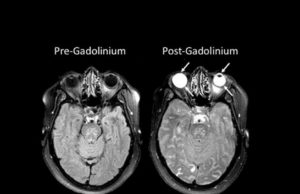

Making the invisible visible: A clearer ‘picture’ of blood vessels in...

Johns Hopkins Medicine researchers have developed and tested a new imaging approach they say will accelerate imaging-based research in the lab by allowing investigators...